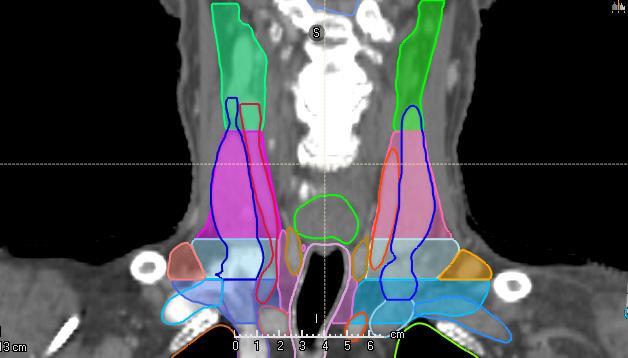

HEAD AND NECK (LYMPH NODE LEVELS) CT

STRUCTURES

LN_Neck_IA

LN_Neck _IB_L

LN_Neck _IB_R

LN_Neck _II_L

LN_Neck _II_R

LN_Neck _III_L

LN_Neck _III_R

LN_Neck _IVA_L

LN_Neck _VAB_L

LN_Neck _VAB_R

LN_Neck _VC_L

LN_Neck _VC_R

LN_Neck _VIA

LN_Neck _VIB

LN_Neck _VIIA_L

LN_Neck _VIIA_R

LN_Neck _IVA_R LN_Neck _VIIB_L

LN_Neck _IVB_L

LN_Neck _IVB_R

LN_Neck _VIIB_R

LN_Neck_IA- LN_Neck_VIIB Grégoire [18]